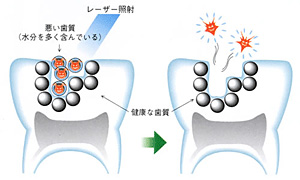

特徴3:レーザーと薬剤を活用した殺菌療法

歯周ポケット内の細菌を効率的に抑制するために、当院ではレーザー機器や特定の薬剤を組み合わせた殺菌療法を採用しています。レーザーを照射することで歯ぐきへの負担を軽減しながら、ピンポイントに細菌を死滅させることが可能です。

<効果1 治療時間の大幅な短縮>

従来の歯周病治療では、歯周病菌の温床となっている歯石を「手作業」で削っていましたので、どうしても時間が掛かってしまい、短時間での治療を希望されるビジネスマンの方にとっては負担の大きなものでした。それに対して、歯科用レーザーには水分を蒸散させる効果があり、水分を多く含んでいる歯石は瞬時に光分解されるため、治療時間が大幅に短縮されます。また、レーザーを使うことで、従来法では届きづらかった深いポケットや複雑な形態のポケットにも到達殺菌することが可能となり、治療効果は格段に高まります。

<効果2 殺菌効果>

従来の歯周病治療では取り除くことが難しいとされていた歯周病が出す毒素(内毒素)の除去さえも、殺菌効果を持つ歯科用レーザーにとっては簡単です。また、治療と同時に患部への殺菌・消毒効果もありますので、治癒経過も非常に良好になります。

<効果3 痛みを抑えた処置が期待できます(個人差あり)>

レーザー光には強いエネルギーがあり、1,000度を超える熱が発生しますが、わずか1万分の3秒という短い単位で照射されるため、痛みの軽減が期待できます。麻酔を用いなくても治療できるケースもありますが、痛みの感じ方には個人差があります。